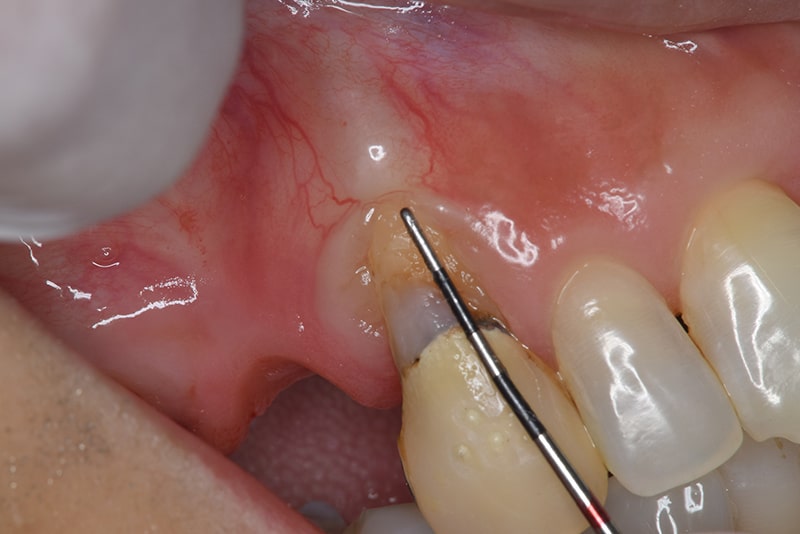

術中

根面被覆(Root coverage)口蓋(上顎)から歯肉を採取し、露出している根面に歯肉を移植し被覆。